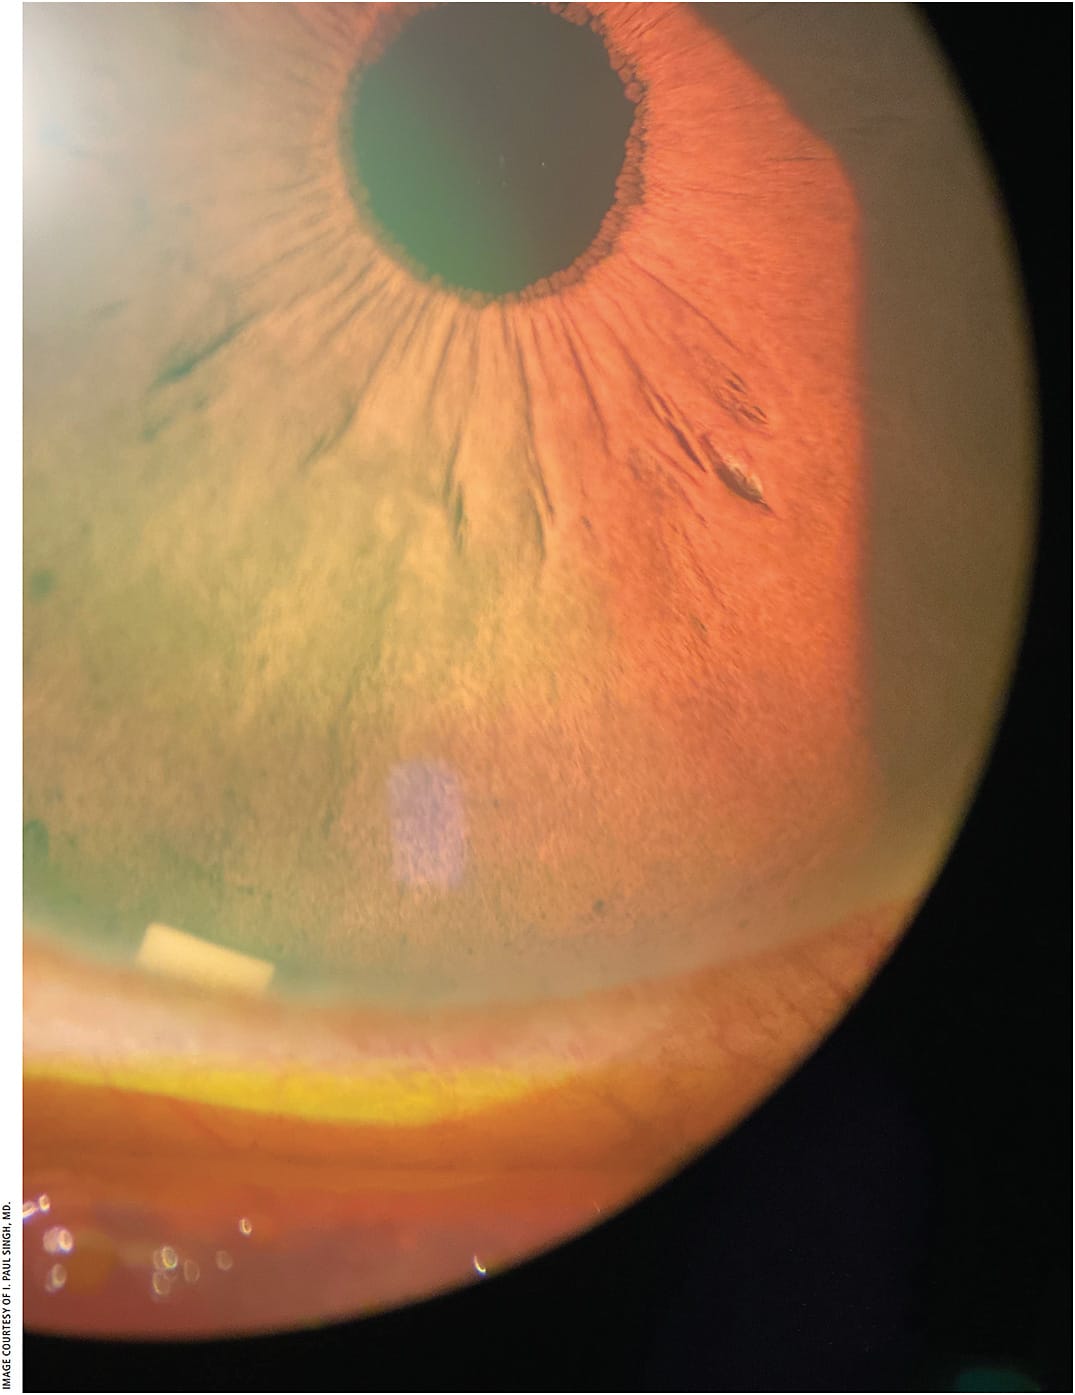

Earlier this year, the FDA approved Durysta (bimatoprost implant; Allergan), the first intracameral, sustained-release implant indicated to reduce IOP in patients with open-angle glaucoma or ocular hypertension (Figure 1).3

“Durysta consists of a small biodegradable pellet that releases 10 mcg of bimatoprost into the eye over about 4 months,” Dr. Singh explains. “In some studies, up to 25% of patients achieved two years of efficacy with just one implant.4 Being able to implant a sustained-release antiglaucoma medication at the time of or after a standalone MIGS increases our chances of reducing the number of topical medications a patient may need.”